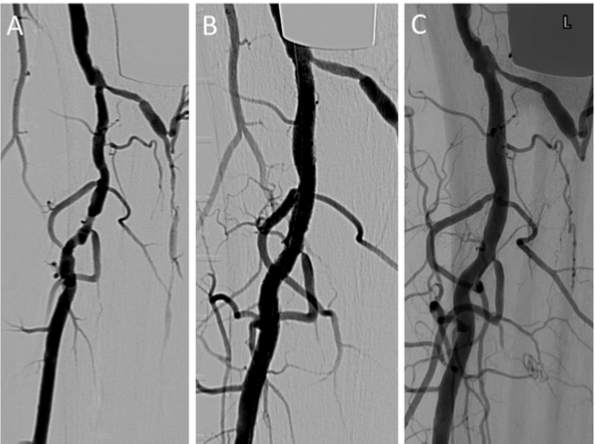

The longest follow-up study was published in 2020 by our group at Sydney’s Prince of Wales Hospital.28 We enrolled 48 patients, treating 55 limbs (72.7% CLI) with 71 scaffolds, and followed them with duplex ultrasound for a mean of 35.2 months. Mean lesion length was 20.1 ± 10.8 mm with median percentage of stenosis at 80% and median target vessel diameter measuring 3.0 mm. Mild calcification grade for 43 patients, 9 and 3 for moderate and severe calcification respectively. Binary restenosis was detected in 11/71(15.5%) scaffolds. Primary patency and freedom from clinically driven TLR rates at 12, 24, 36, 48, and 60 months were 90.8%, 90.8%, 79.7%, 76.3%, 72.3% and 97.2%, 97.2%, 90.7%, 90.7%, and 90.7%, respectively. Demonstrating excellent efficacy in shorter lesions. An example of a case with long-term follow-up is given in Figure 2. Similarly, Kum et al demonstrated excellent results in a retrospective study of 41 CLI patients (53 lesions and 69 scaffolds) as part of the DISAPEAR registry. The mean

Figure 2. An angiographic image showing (A) a diffuse stenotic lesion of the tibio-peroneal trunk and peroneal arteries (B) treated with two abutting Absorb drug-eluting resorbable scaffolds. (C) A follow-up angiogram of the same patient 91 months after the procedure demonstrates smooth remodeling of the blood vessel wall with no evidence of restenosis.